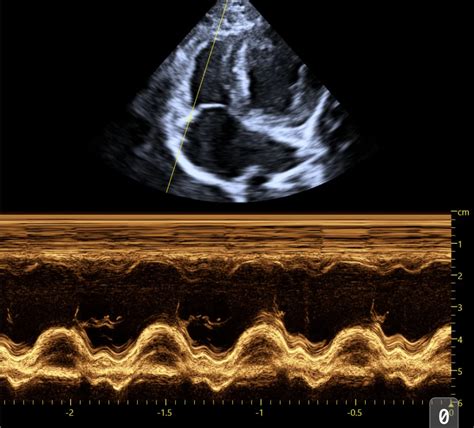

2. The Parasternal Short-Axis View (PSAX)

Next up, we have the parasternal short-axis view , or PSAX. This is like taking a slice through the heart, perpendicular to the long axis. We obtain this view by rotating the probe 90 degrees from the PLAX, still keeping it on the chest wall. The beauty of the PSAX is that it allows us to see the heart’s chambers in cross-section. We can get short-axis views at different levels : the aortic valve level, the mitral valve level, and the papillary muscle level (which is deeper in the ventricle). At the mitral valve level , we see the LV, the LA, and the two leaflets of the mitral valve appearing like a fish mouth. This is super useful for assessing mitral valve morphology and function, especially for conditions like mitral valve dysplasia or degeneration, common in older dogs. At the papillary muscle level , we see the LV cavity and the two papillary muscles within it. This view helps us evaluate the global contractility of the LV free wall and septum. And at the aortic valve level , we see the aorta , the right ventricle (RV) , and the three cusps of the aortic valve. This is great for looking for things like aortic valve stenosis or vegetation (like those nasty endocarditis growths). The PSAX is invaluable for assessing the relative sizes of the ventricles, the thickness of the ventricular walls, and the overall shape of the LV cavity. It helps us confirm findings from the PLAX and identify subtle abnormalities. It gives us a bird’s-eye view of the internal structures, allowing for a comprehensive assessment of the ventricular walls and their synchronized contraction. You can truly appreciate the circularity of the left ventricle here, which is a sign of healthy function, or an elliptical shape which might indicate issues. It’s a fantastic way to get a comprehensive understanding of the heart’s chambers and their immediate surrounding structures.